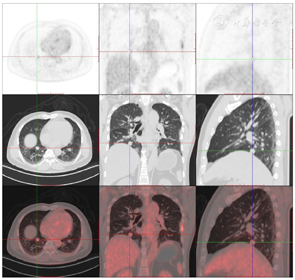

头颅顶可见术后瘢痕,愈合可,后颈可见一长约10 cm术后愈合瘢痕。头颅压痛、包块。发病来,患者神志清,精神可,睡眠可,饮食及大小便正常,体重无明显变化。2021年10月8日行PET-CT示左侧额顶部颅骨术后改变;左侧颞极片状高密度影并邻近骨质破坏,代谢增高(图A);左前纵膈肿块,代谢增高(图B);双肺散在结节,代谢轻度增高(图C);右侧锁骨、左侧第6肋,胸9-腰1、3椎体及其附件骨、双侧髂骨及双侧股骨近端多发混合型骨质破坏,代谢不同程度增高,考虑多发转移瘤(图D,图E,图F);2021年10月10日复查CT示右肺下叶可见结节影,直径约1.5 cm,增强扫描轻度强化;前上纵膈可见类圆形软组织密度影,边界清楚,大小约4.4 cm×3.3 cm,增强扫描轻度强化。于2021年10月11日在局部浸润麻醉下行CT引导下经皮纵膈占位穿刺活检术。病理结果示:肺穿刺组织内见恶性肿瘤,符合转移性间变性脑膜瘤。2021年10月13日MRI示:多发胸椎椎体及附件、所扫及L1椎体异常信号,结合病史,考虑为转移瘤可能。